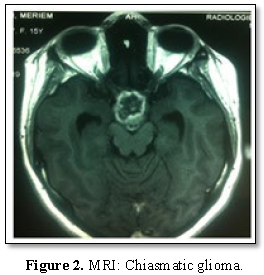

Results: The mean age of patients at the time of diagnosis was 12.67 years (3-27 years) with a slight male predominance (58%). The main functional signs was the decrease of visual acuity (75% of cases), followed by intracranial hypertension syndrome with 58.3%, neurological disorders (hemiplegia and epilepsy) in 33.3% and endocrine signs (amenorrhea) in 16.7% of cases. Tumors were solid in 25% of cases and Solido-cystic in 75% of cases on MRI. Surgical removal was partial in 11 patients (92%) and total in 1 patient whose lesion affected only the optic nerve. Visual improvement was noted in 9 patients (75%), no neurological worsening or operative death was reported. Only one patient had presented 27 months after surgery, epilepsy leading to the death.

The 12 patients were operated through fronto-pterional or sub-frontal approach. Surgical removal was partial in 11 patients with chiasmatic and opto-chiasmatic glioma (92%). One patient whose lesion affected only the left optic nerve had total resection associated to its sacrifice. All tumors were pilocytic astrocytomas (grade I WHO classification). No postoperative complications were noted. Two patients received radiotherapy (1 preoperatively and 1 postoperatively). Two patients received chemotherapy postoperatively. Visual improvement was reported in 9 patients (75%). No visual or neurological worsening was described. Only one patient had presented 27 months after surgery, epilepsy leading to the death. The results of the follow-up are illustrated in Table 1.

Optic pathway gliomas represents 0.5 to 5.1% of all intracranial tumors [3,7] but 65% of primary tumors in the optic nerve [8]. This frequency is higher in children with neurofibromatosis type 1 (up to 30%) [4]. The average age was 12.67 years. In comparison, one of the most comprehensive studies published by DUTTON about 2297 cases; the average age was 8.8 years of which 90% of cases were under 20 years. The mean time to diagnosis is 3 years for our patients with optic nerve glioma, 5 months for those with chiasmal glioma and 14.8 months for those with opto-chiasmatic involvement [9]. In the BATAINI series [10], the average time between the first symptoms and diagnosis is estimated at 14.6 months. This delay varies according to the nature of the clinical signs and the tumor topography. According to Appeleton [11], only exophthalmia allows early diagnosis because it is easily recognizable. Our series reports a male predominance. This is not corroborated in the various series, which do not find either predominance of sex [12] or on the contrary, a slight female predominance [13]. Exophthalmia, visual loss and strabismus are the three most common symptoms [6]. The decrease of the visual acuity is the first revealing sign. It is usually a slow, gradual decrease that can be uni or bilateral [11,14]. When it is present, it is often very severe. In fact, 80% of Optic pathway gliomas have a low visual acuity less than 1/10 according to RUSH [15] and 67% of patients counted only the fingers, in the JAKOBIEC series [16]. It should be noted that visual acuity is not always quantifiable in very young children because of their lack of “cooperation” and it is a sign that is not constant. Papilledema was present in 2 cases (17%) and optic atrophy was noted in 2 others. Wright [17] notes in his study that papilledema is mainly present in evolutionary tumors. Oculomotor disorders are infrequent and occur in only 17.6% of optic pathway gliomas [18]. However intracranial hypertension (ICH) is the most common tell-tale sign of optic pathway gliomas by hydrocephalus [19]. It was noted in 7 of our patients (58%). ICH is a pejorative sign as reported by a recent study which shows that patients with ICH have a low survival rate compared to patients who do not have this symptom [6]. It may appear in the course of evolution and is related to the posterior chiasmatic extension, blocking the third ventricle and Monro's hole. Other neurological signs (hemiplegia, epilepsy, walking disorder, balance disorder) may sometimes exist [14]. Their presence is a poor prognosis factor. On the other hand, opto-chiasmatic gliomas may be responsible for endocrine disorders by hypothalamic extension (early puberty, Russel syndrome, diabetes insipidus or anterior pituitary insufficiency) [20]. Lund [21] considers that the use of visual evoked response is more interesting than neuroradiological techniques for the detection of optic pathway gliomas, as they do not require sedation and can play an important role in monitoring in order to evaluate the visual function, residual visualization after surgery or for children for whom no treatment has been recommended. MRI allows a better diagnosisto monitor tumor progression and treatment response. Regarding the tumor localization, it is difficult to obtain reliable statistics. However, it appears that 25% of gliomas remain confined to the optic nerve and 75% reach the chiasm while extension to the optic nerve head and intraocular structures is rare [24]. Despite extensive literature, the treatment of optic pathway gliomas is controversial because of too small series, too short follow-ups, and the heterogeneity of the groups. Similarly, the unpredictable evolution of these tumors justifies the different therapeutic options proposed by different authors, ranging from simple observation to radiotherapy, chemotherapy, surgical resection and/or the combination of these different means [2,6,12,13]. The current approach is to start treatment when visual impairment is evident and/or tumor enlargement on imaging. In case of optic nerve glioma, the surgery must be as radical as possible and offer a definitive cure [23]. The decision to resect the optic nerve should be made in case of blindness and when the tumor is responsible for severe exophthalmos. Otherwise, in case of preserved or partially preserved vision or moderate exophthalmia, the “wait and see” policy should be adopted first [6]. The size and extent of the tumor influences the surgical management.When the tumor affects the optic chiasm, with an anterior extension to the optic nerves or posterior to the hypothalamus, the role of the surgery is not well clarified. These lesions respond better to radiotherapy [22]. To avoid worsening of visual function, a limited biopsy before radiotherapy is the best choice [6,27]. In our series, 11 patients underwent partial excision of the tumor with a visual improvement in 9 patients (75%). In addition, surgery can be indicated in case of differential diagnosis with others sellar tumors as craniopharyngioma. In case of surgery, blindness threatens 66.6% of children treated by partial resection [18,23]. Immediate postoperative complications are poorly documented in the literature but their frequency tends to decrease due to the advent of new neurosurgical techniques [24]. We did not note any of them in our series. Most of optic pathway gliomas are benign pilocytic and pilomyxoid astrocytomas [3].The role of radiotherapy is highly controversial and its usefulness remains to be proven. Some series report an improvement in visual acuity after radiotherapy [15]. Pierce [17], obtained 91% of good visual results after radiotherapy. However, other studies showed no improvement in survival or visual acuity and some researchers have even warned of the dangerous effects of radiation in children [25,26]. It is used at doses ranging from 4500 cGy for tumors limited to chiasma and 5500-6000 cGy for tumors invading the hypothalamus [27]. Chemotherapy, by offering a first-line treatment, may have a therapeutic effect, at least by delaying the indication of radiotherapy. Regarding the role of chemotherapy, Petronio [28] reports that all those for whom the tumor responded to chemotherapy had an improvement or stabilization of visual acuity. But other authors report that chemotherapy has not yet sufficient evidence of efficacy to be proposed as the first therapeutic choice [29].